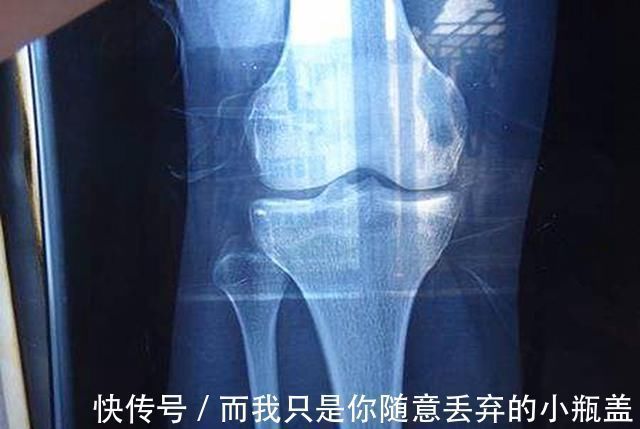

检查结果显示,孩子竟然是“性早熟”导致的骨骼线提前闭合。这也就意味着孩子的身高可能之后都要定格在一米二了。